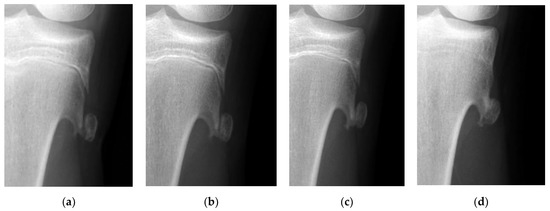

The mean time to return to the original sports activities was 2.3 weeks (range 1–4 weeks) in the surgery group. In contrast, the longest time required to return to original sports activities was 15 weeks in the one patient in the observation group. Surgery was not performed since pain subsided within 4 weeks after injury. However, this patient could not return to tennis due to the discomfort caused by a prolonged union; it took as long as 54 weeks to achieve partial union (Figure 3).

Figure 3.

The radiographic views show sequential changes of the displacement of a fractured osteochondroma in the tibia. (a) Displacement of the fractured tibial osteochondroma is found in a 13-years-old girl who is a tennis player. (b) Union cannot be observed 4 weeks after the injury. (c) Partial union is achieved 1 year after the injury. (d) Complete union can be observed 5 years after the injury.